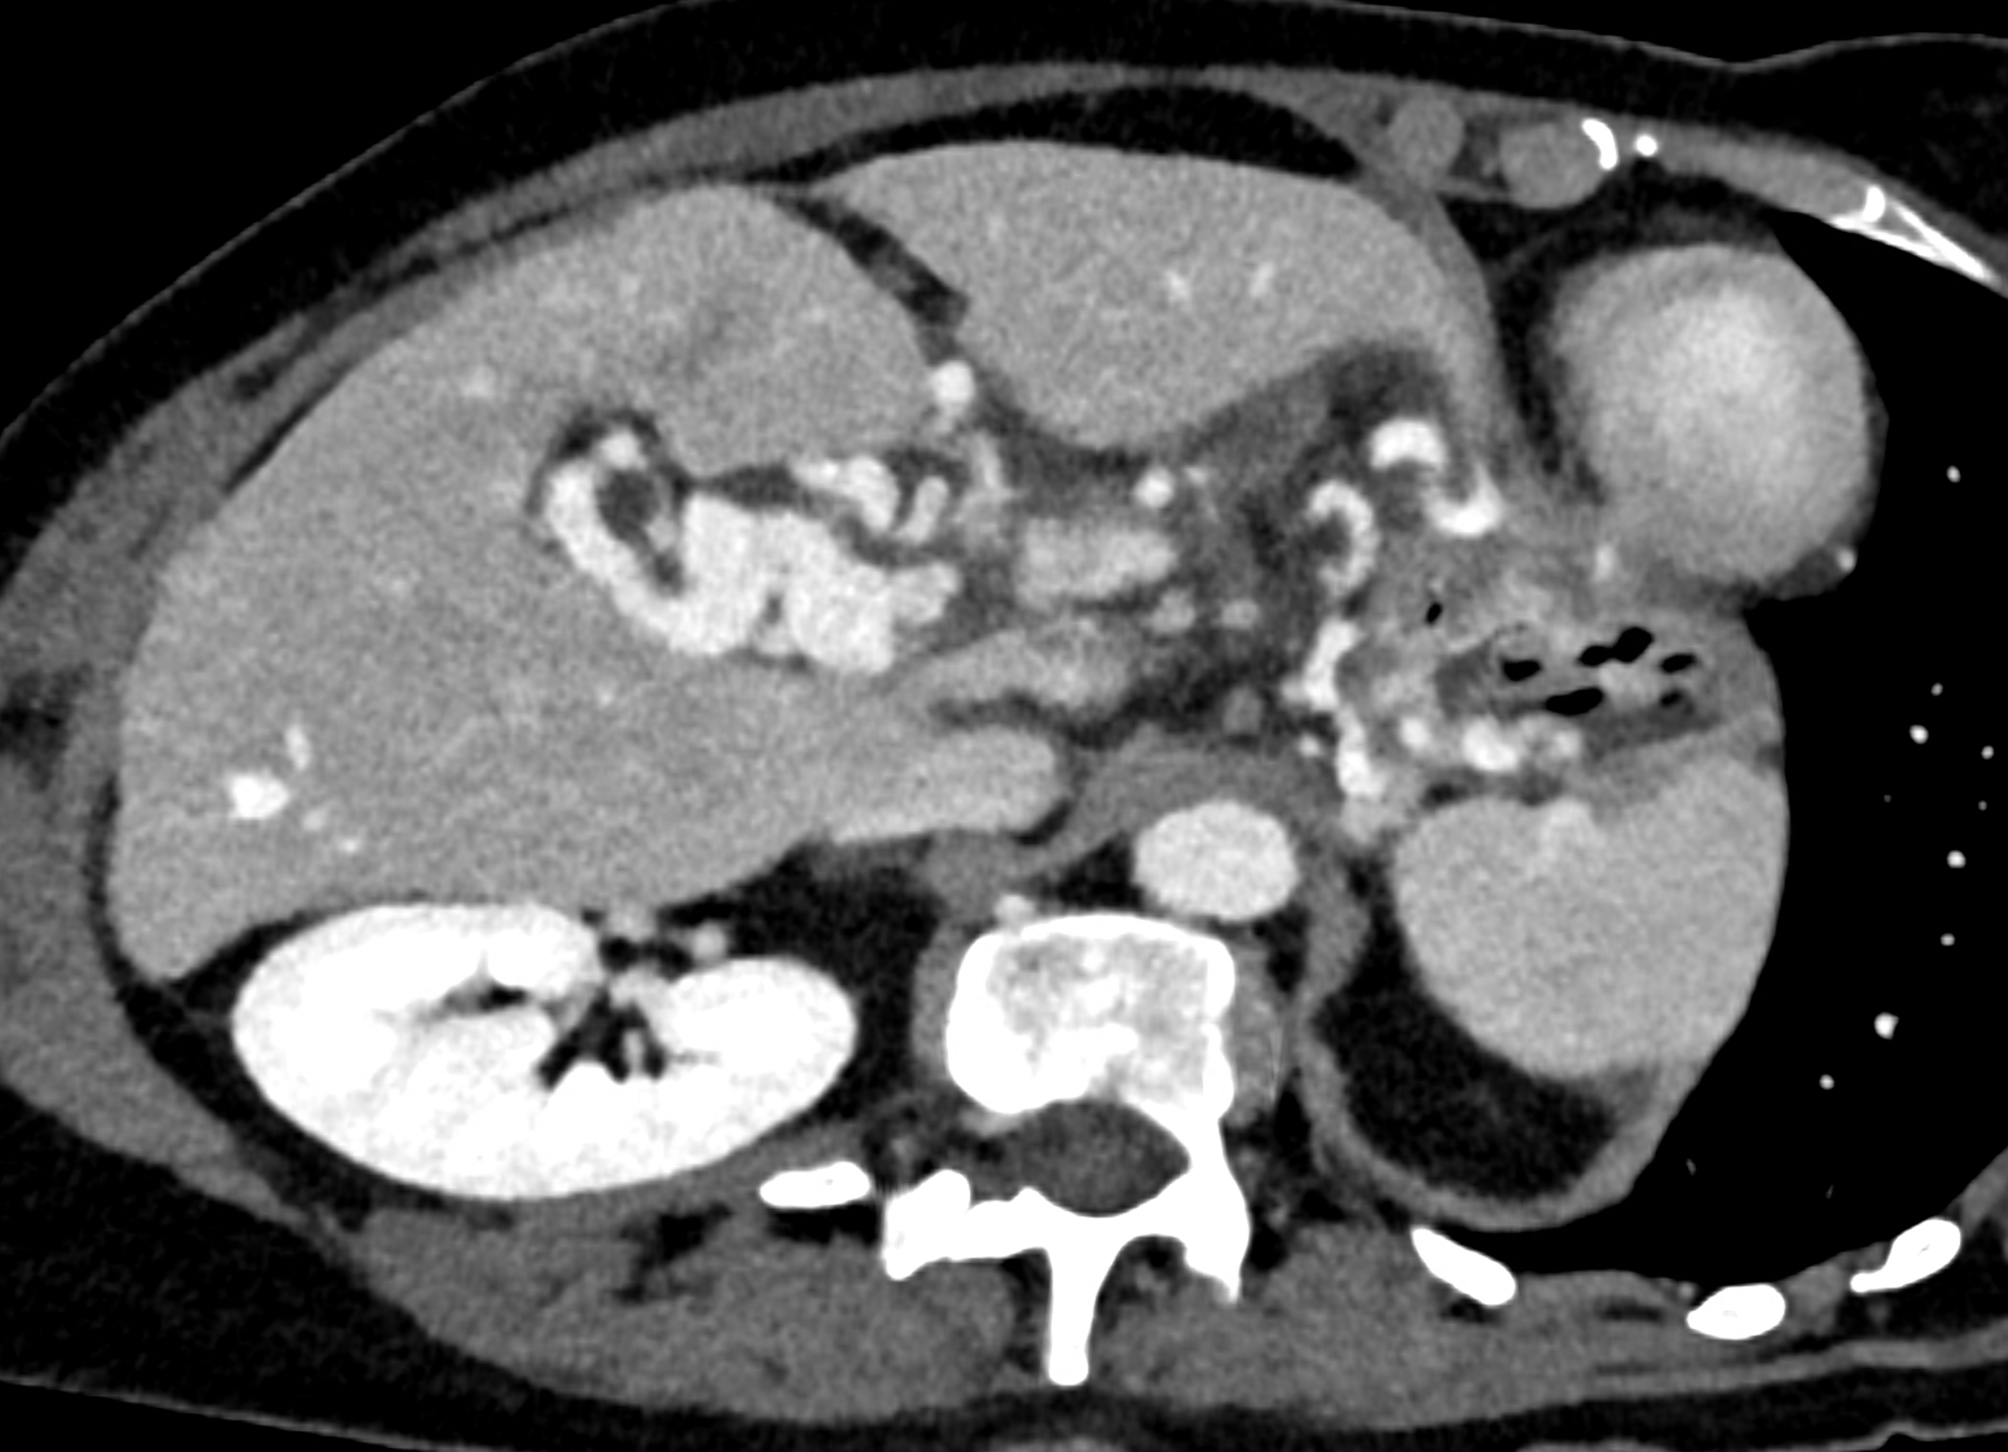

During CT, the most significant phase is the portal phase of liver enhancement, when portal biliopathy is associated with dilation of the bile duct wall, which is significantly enhanced with the contrast agent in the case of dilation of the epicholedochal plexus, or there is a combination with varicose veins around the saturated bile duct wall (dilatation of the paracholedochal plexus). Other possibilities include enhancement of only the paracholedochal plexus and a combination of dilatation of the paracholedochal plexus with cavernous remodelling of the portal vein itself.

The spectral characteristics of data obtained using photon-counting CT allow optimization of the signal from the venous system, thereby increasing the difference between saturated collaterals and the surrounding area. At the same time, excellent spatial resolution aids in the visualization of bile ducts filled with bile.

A patient with chronic pancreatitis and chronically occluded portal vein. The bile ducts have a significantly dilated wall, from the trunk, through the stump of the cystic duct, to the right and especially the left branch of the hepatic duct. At the same time, a large pseudocyst in the pancreas, dilatation of the pancreatic duct, and chromic occlusion of the superior mesenteric vein, splenic vein, and portal vein trunk are evident. Along with portal biliopathy, there is also arixy of the cardia and esophagus, as well as cavernous remodeling of the portal circulation itself.

dilated veins in the wall of left hepatic duct

dilated veins in the wall of left hepatic duct and paralel veins of portal cavernous transformation

dilated collaterals in hepatoduodenal ligament partially portal biliopathy, partially cavernous transformation

dilated veins in the wall of common hepatic duct